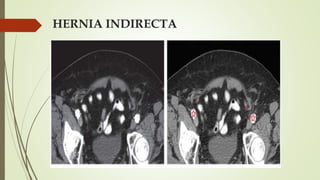

HERNIA INDIRECTA

 Pasa superolateral a vaso epigástrico inferior  lateral y medial

siguiendo el CI

 Se muestra con el contenido habitual del CI, no se comprime ni

distorsiona